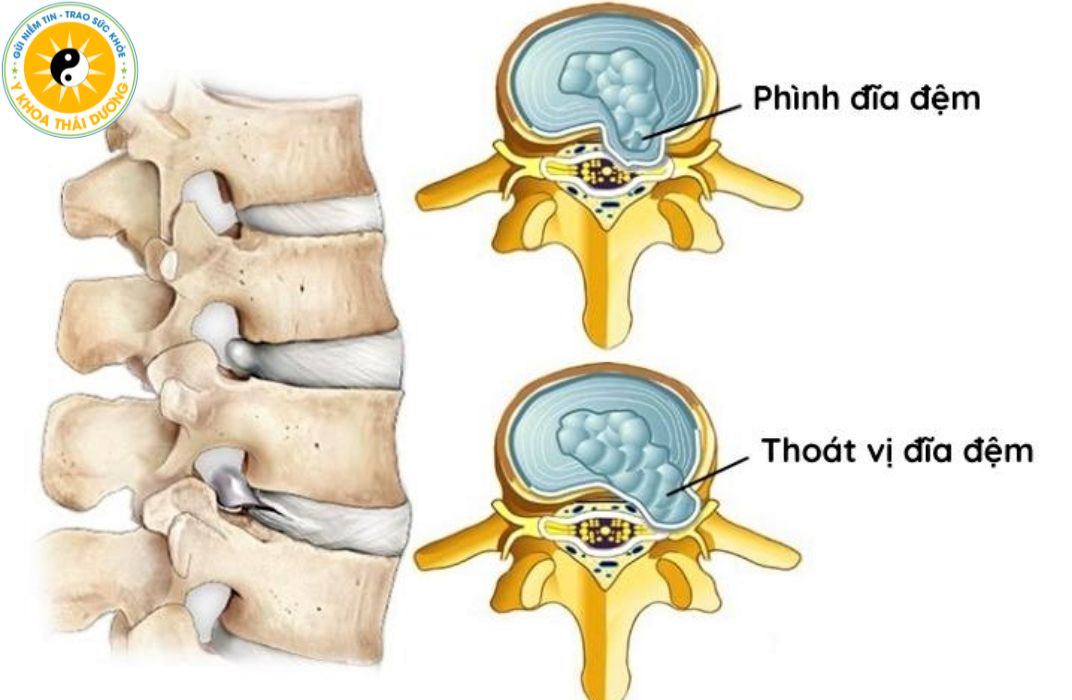

Nguyên nhân gây phình lồi đĩa đệm là gì? Phác đồ điều trị

Phình lồi đĩa đệm là giai đoạn sớm của thoát vị đĩa đệm, khi bao...